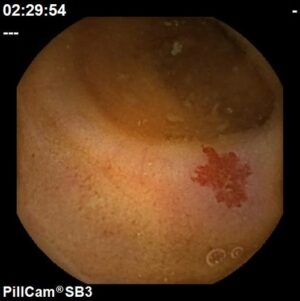

Angiectasia do cólon

Hospital Senhora da Oliveira (Guimarães)